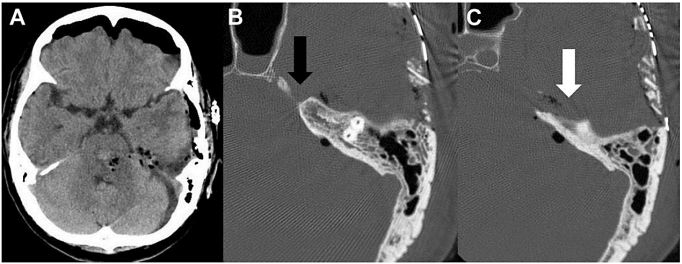

63岁女性患者,突然意识丧失。入院时GCS评分10分,右侧肢体轻偏瘫,左侧展神经(Ⅵ CN)和左侧面神经(Ⅶ CN)麻痹(House-Brackmann分级:5)。CT显示脑桥出血(图1)。术前诊断原发性桥脑出血。采用iCTPA手术。患者仰卧位,头部旋转90°,取左耳周围U形皮肤切口,逐层切开颞肌筋膜和颅骨膜,剥离颞肌,行左颞底开颅。不切除乳突和乙状窦骨质。中颅底上方U 形切开硬膜,保护颞叶和Labbe静脉,沿小脑幕游离缘释放环池脑脊液,以松弛颞叶。在导航下仔细探查中颅窝底,识别与KT和TT相关的解剖标记,包括弓状隆起和下颌神经。切开中颅窝底的硬膜,显露KT和TT及岩浅大神经。使用超声骨刀按需切除骨质。结扎岩上窦,切开小脑幕,打开Meckel囊以显露三叉神经,以及暴露桥脑的前外侧面。导航下,于距离血肿最近处切开脑干,清除血肿(图2)。

术后即刻CT显示,血肿清除(图3)。术后两周,患者GCS评分15;右侧运动功能:肌力4级;左面神经功能:House-Brackmann分级:5→2。